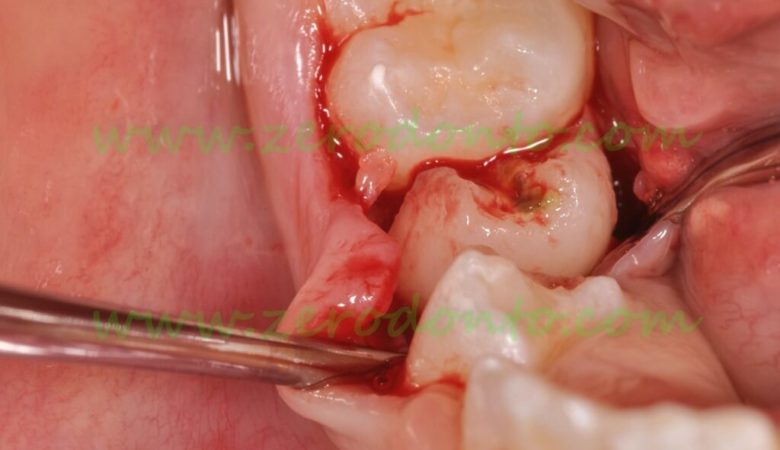

Oral Surgery

Digital imaging, surgical microscopes